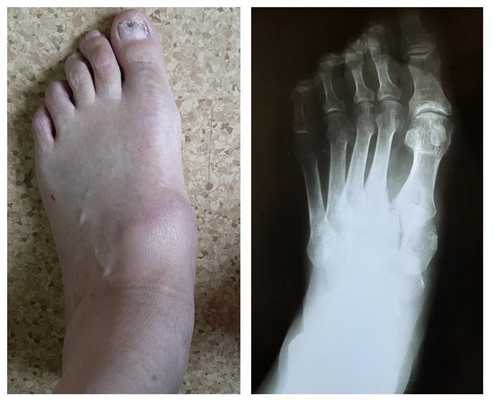

У нашей пациентки произошёл гомолатеральный вывих, то есть все плюсневые кости сместились в наружном направлении. На стандартных рентгенограммах в свежих случаях данные повреждения пропускают практически в 100% случаев. Необходимо делать рентгенограммы обеих стоп стоя с нагрузкой весом тела и даже в такой ситуации неопытный глаз пропустит травму.

Клинически это проявляется постоянными болями в средней части стопы, коллапсом продольного свода, переходом нагрузки на опустившийся вниз средний отдел стопы, отведением всего переднего отдела стопы в наружную сторону.

Передний отдел стопы распластан и отведён кнаружи, по внутреннему краю стопы в средней её части формируется горб - вершиной деформации становится медиальная клиновидная кость, её дистальная суставная площадка.

Внешний вид стопы после хирургического вмешательства, Деформация среднего отдела стопы устранена, продольный свод восстановлен. Имеющаяся деформация переднего отдела будет устраняться после заживления среднего отдела не ранее 3 месяцев от первой операции.